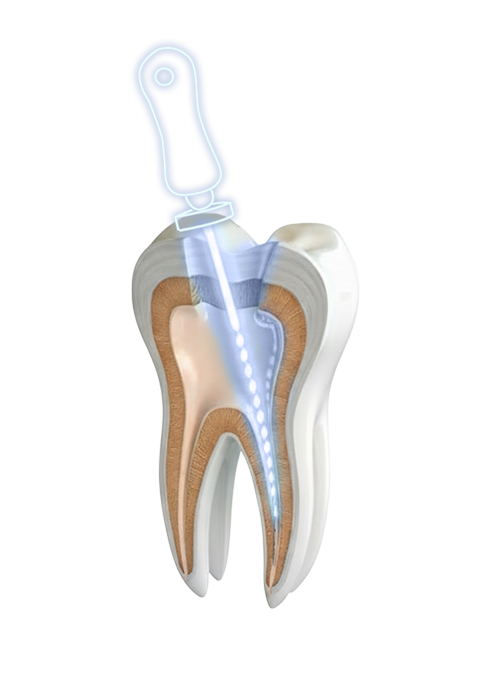

08 Endodontics (Root Canal Treatment)

A root canal (also called endodontic treatment) is a dental procedure that aims to save an infected or severely damaged tooth by removing the dental pulp (the soft tissue inside the tooth containing the nerves and blood vessels), then cleaning, disinfecting, and sealing the inside of the tooth.

Is it painful?

No, because the anesthesia is very effective. There may be slight pain or sensitivity after the treatment, but it is generally well controlled by painkillers.

What if we do nothing?

If a dental infection is not treated:

- It can spread to the bone and tissues around the tooth,

- Cause an abscess,

- And lead to the loss of the tooth.

- Cause general health problems